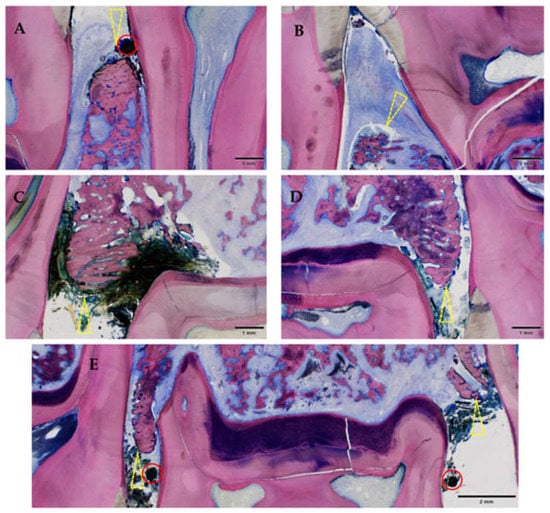

3.2.2. Histological Evaluation